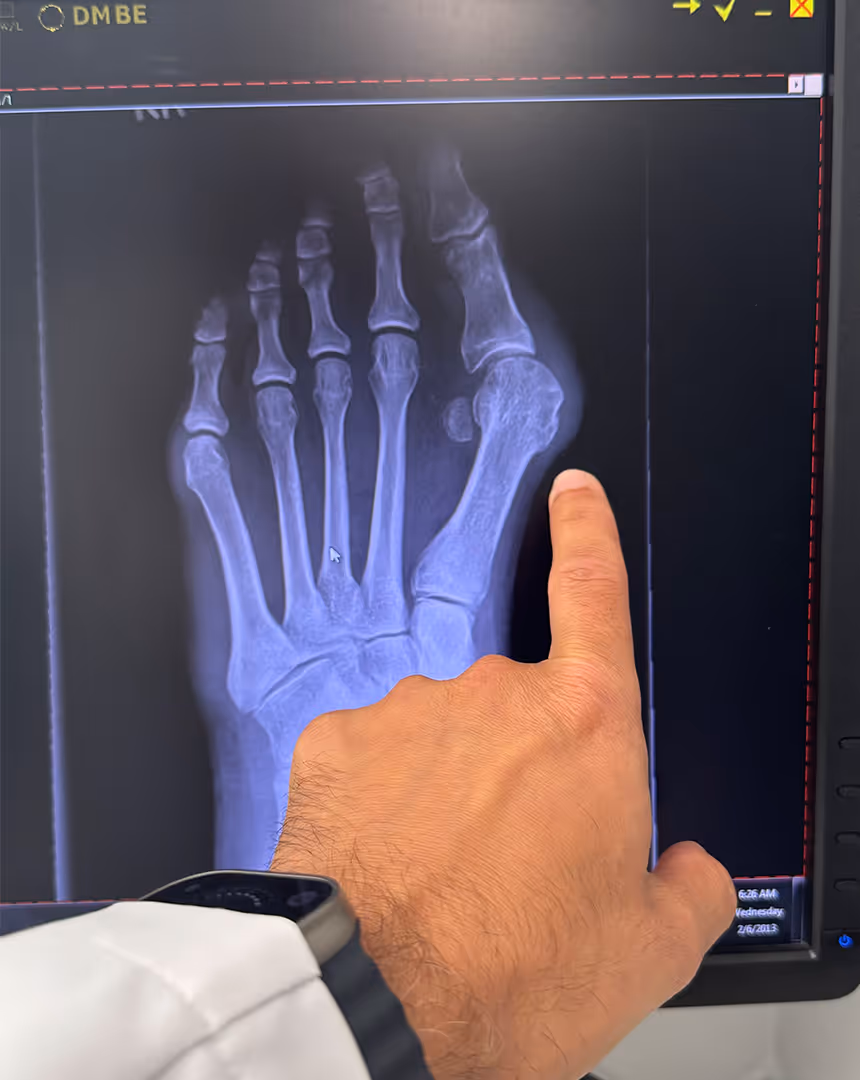

Diagnosis of Bunions

Diagnosing bunions requires a detailed evaluation to determine the severity of the condition and any associated issues. Dr. Soomekh uses the following advanced diagnostic methods: